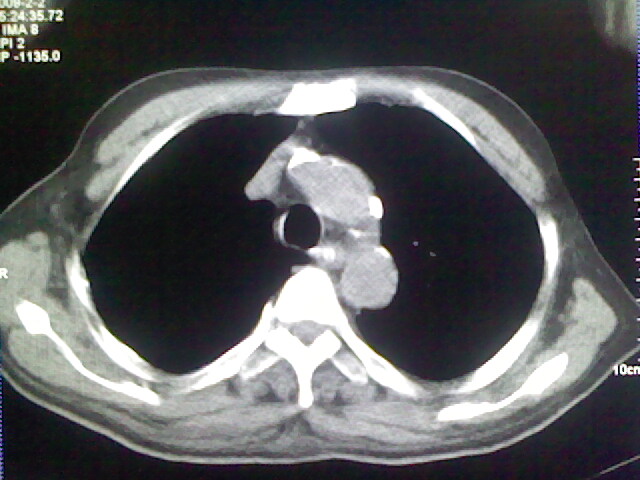

男,70岁,脑出血,长期卧床,左侧背部可触及肿块

右肺病灶考虑炎症性。

右肺病灶考虑炎症性

考虑右肺及左肺下叶炎症。

右肺上叶前段病呈楔形,其尖端指向肺门,考虑肺动脉栓塞可能性大.